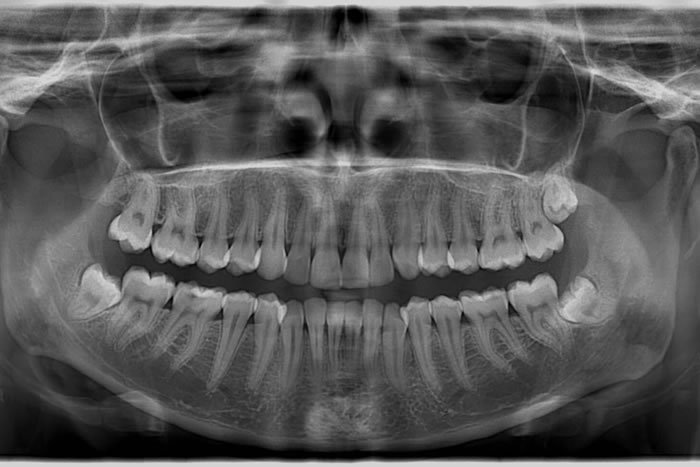

Dental Radyoloji

Dental radyoloji, diş ve çene sağlığını değerlendirmek, tedavi planlaması yapmak ve potansiyel sorunları...